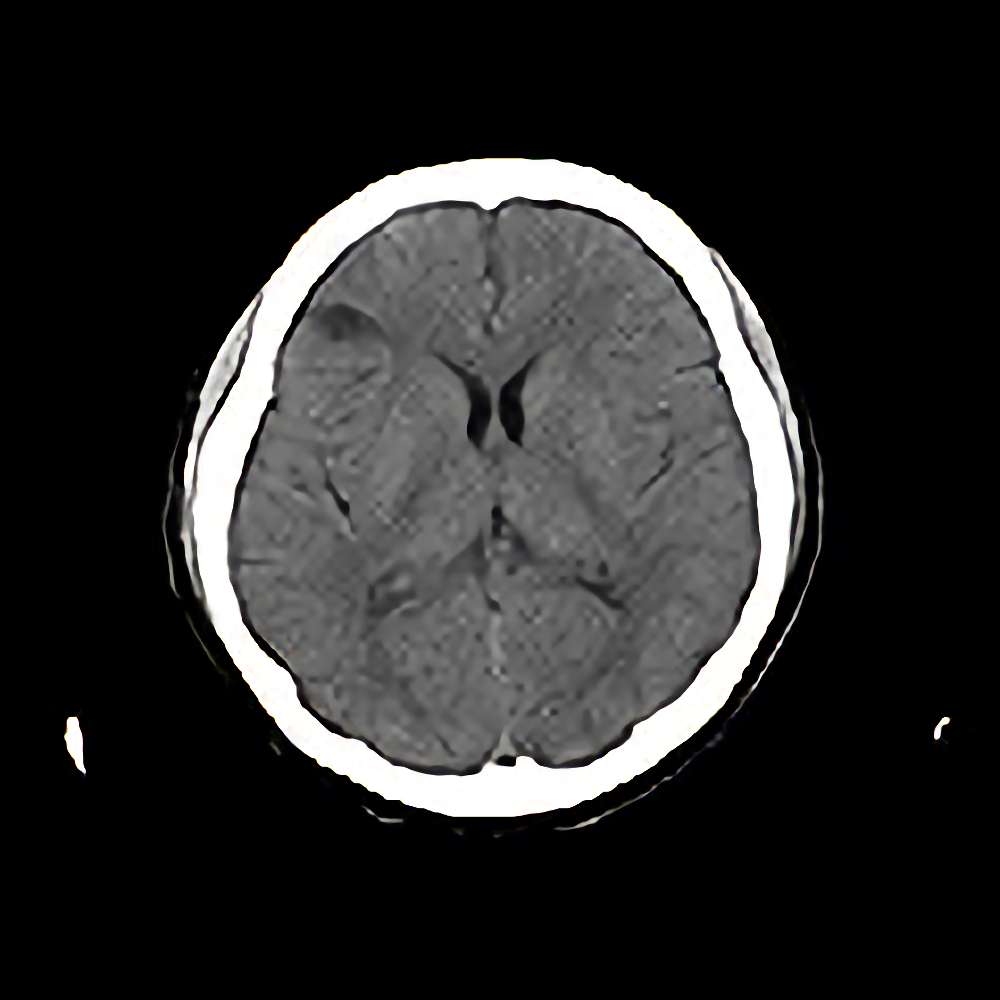

海綿状血管腫

断層撮影

手術前1

No.’12_91 手術前1

No.’12_91 手術後